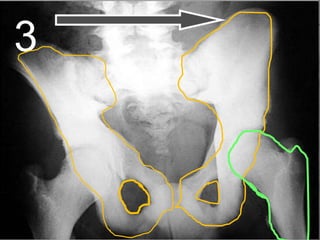

• Your pelvis helps protect the bladder,

intestines, and reproductive organs in

women.